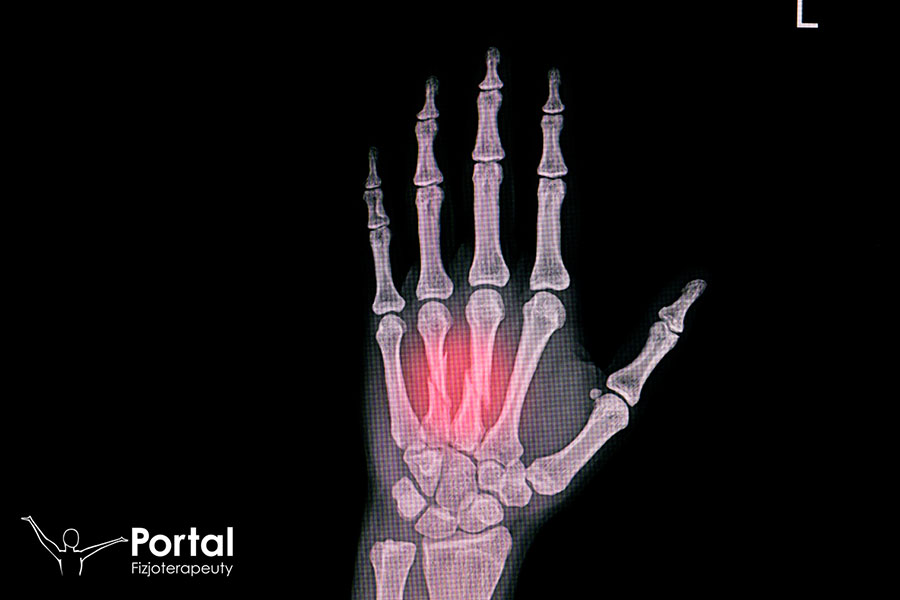

Złamanie ręki polega na częściowym lub całkowitym przerwaniu ciągłości tkanki kostnej w obrębie ręki. Mianem ręki nazywamy część kończyny górnej